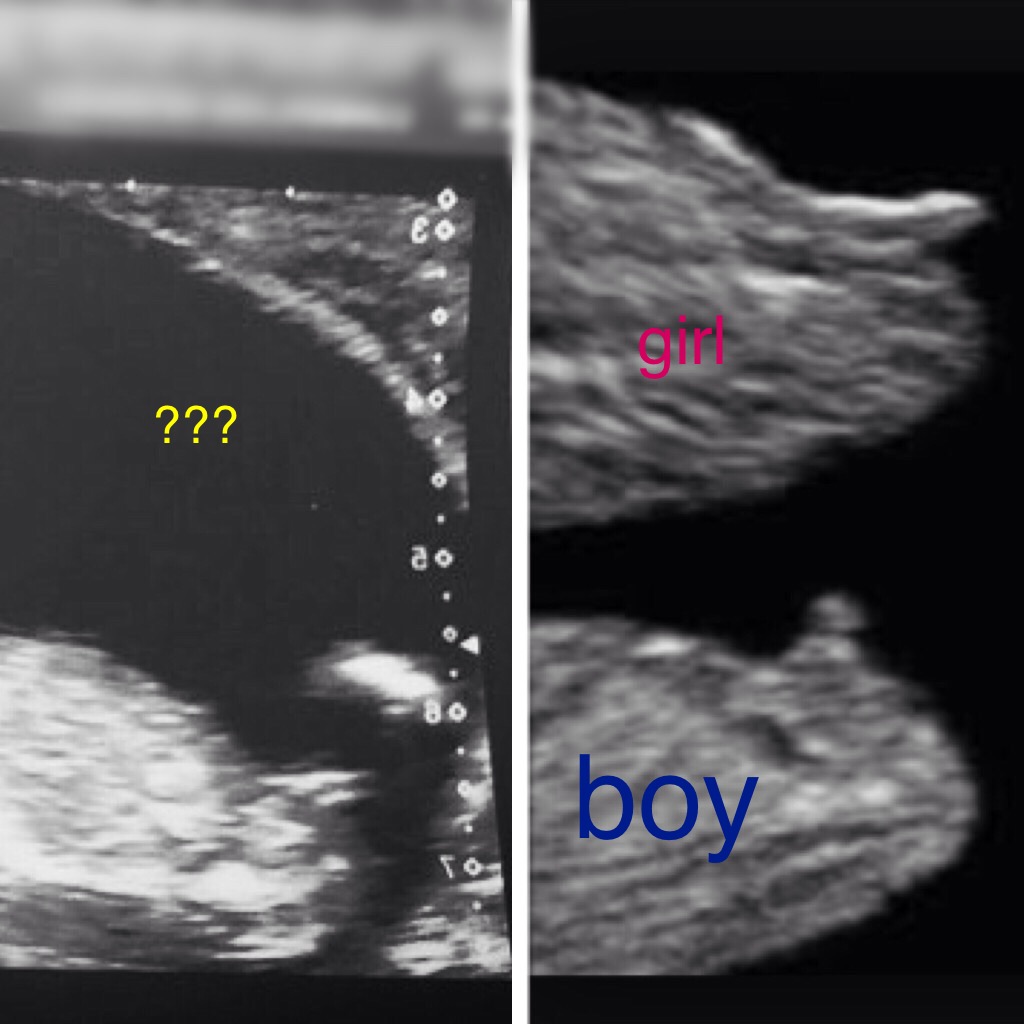

And again above it shows how the flat bright white line nub of a boy can often appear as shorter as his outer line has shrunk back to testicles and his inner white nub line has angled up.

Attachment 10890

Now the angled up white nub line on a boy can often be missed if the sonographer takes your picture at just a small angle off of flat. The two ultra sound pics above show the same baby but slightly different angle of pic so hiding that boy nub! Which is why again it is important that you keep your eyes peeled incase you are only given the bottom pic:agree: